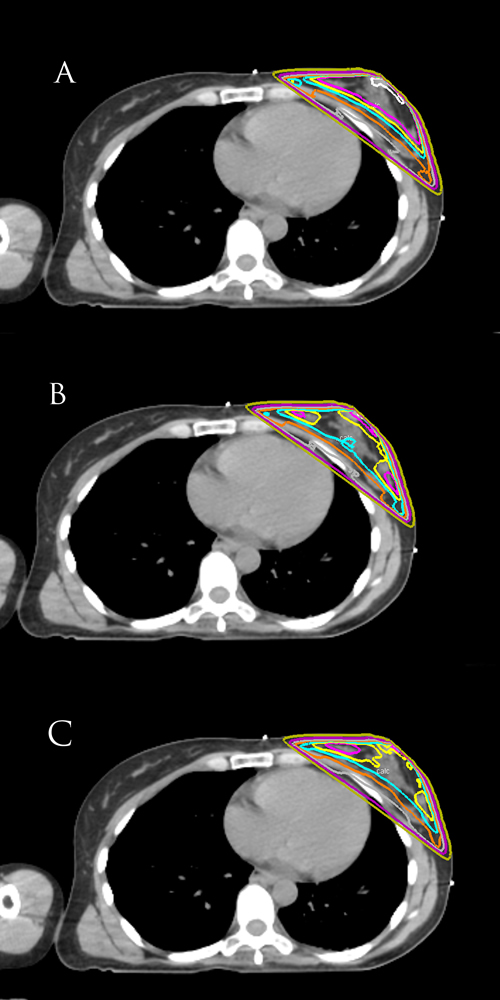

What set of isodose curves best displays homogeneous coverage for left-sided breast cancer?